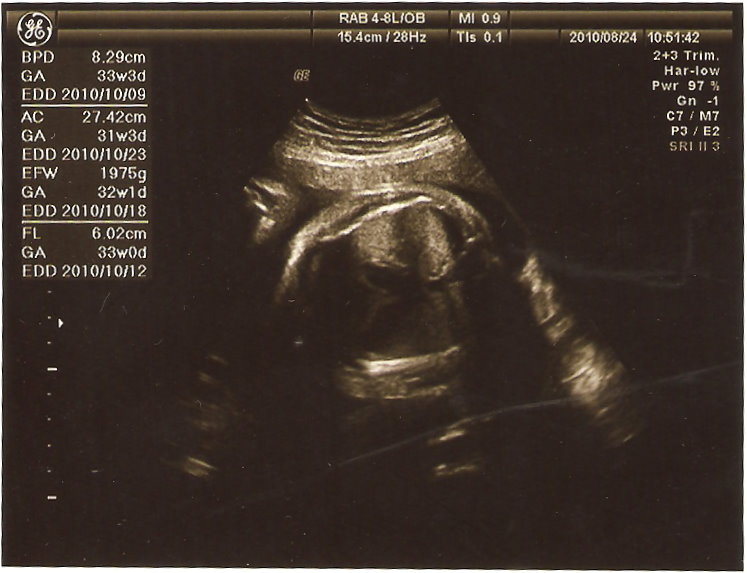

這次BPD 8.29cm(超前10天),AC 27.42cm(落後4天)

EFW 1975g(早一天,不過醫生說他稍重,在正常值內但要注意一下)

FL 6.02cm(提前一週,沒之前那麼多了

不過我希望他頭不要太大,體重也不要太重,醫生說我現在胎位正了,也不會再轉了